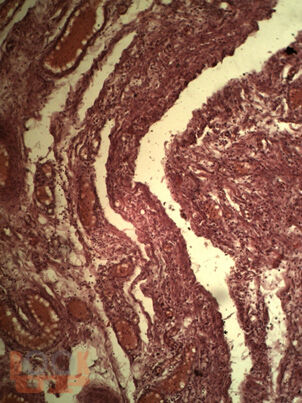

В монографии изложены данные отечественных и зарубежных авторов, результаты собственных исследований, посвященных современным проблемам воспалительных заболеваний органов малого таза (ВЗОМТ). Особое внимание уделено комплексному методу лечения и реабилитации осложненных форм ВЗОМТ с включением квантовой терапии. В монографии представлены собственные результаты клинико-лабораторных, инструментальных методов обследования пациенток с гнойными тубоовариальными образованиями, а также результаты применения квантовой терапии.